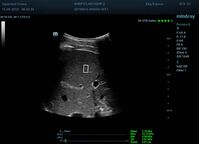

Определение плотности печени. Не ошибся ли оператор при измерении эластических свойств печени? Для оценки критериев качества предусмотрен индекс MBT, который покажет насколько «твердой» была рука оператора и двигалась ли печень. При MBT 5* рука тверда и показатели достоверны. Для оценки качества результатов используется IQR индекс, отображающий колебания показателей в точке измерения при расчете медианы. Показатели при IQR <30% считаются приемлемыми. Техника сканирования через межреберные промежутки требует размещение окна интереса на несколько сантиметром ниже капсулы, для исключения эффекта реверберации. Установка ROI на паренхиму без захвата сосудов, для исключения погрешностей измерения.

Стадия фиброза определяется по системе METAVIR Staging, построенной на данных биопсии и сопоставлении с данными эластографии. Своевременная диагностика фиброза, и начало его лечения, залог благоприятного исхода заболевания.